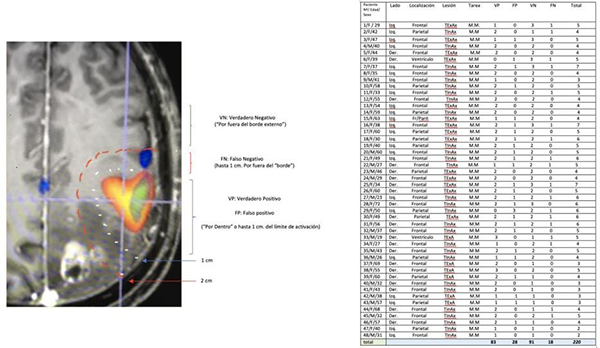

Se utilizó un test binario (tabla 2 x 2) para validar la respuesta motora en el área de activación de la RMfm. El test de referencia para validar la prueba fue la electroestimulación cortical directa (ECD).

Las respuestas a la ECD (Estimulación Cortical Directa) se clasificaron en este trabajo como: 1 (VP): verdadero positivo: cuando se observa respuesta motora por ECD dentro del área de activación de la RMfm, o hasta un máximo de 1 cm por afuera del “borde”, 2 (VN): verdadero negativo cuando hubo ausencia de respuesta por fuera del “borde” del área de activación de la RMfm, (3)FP: falso positivo ausencia de respuesta motora por ECD dentro del área de activación de la RMfm (ó su borde), 4: falso negativo la presencia de respuesta motora por ECD 1 cm por fuera del “borde del área de activación BOLD.

Resultados de la prueba (Tabla Nº1)

Se realizaron un total de 220 (tabla Nº2) registros luego las respuestas se distribuyeron para su análisis estadístico en una tabla 2 x 2 (tabla N° 3):